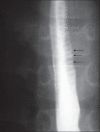

Eosinophilic esophagitis (EE) is an inflammatory condition characterized by intense eosinophilic infiltration of the esophagus. EE is frequently misdiagnosed as gastroesophageal reflux disease. Here, we present a child with EE and a characteristic endoscopic finding, "ringed esophagus". An 11-year-old Saudi boy presented with dysphagia for 1 year. He had experienced an intermittent sensation of solid food sticking in his chest, which was relieved by drinking liquids. A barium swallow excluded anatomical causes of dysphagia, but revealed multiple-ringed esophagus. Endoscopy showed a furrowing and trachealizing appearance of the entire esophagus. Hisologically, extensive eosinophilic infiltration was a feature in biopsies obtained from the esophagus. The child responded well to a 2-month course of inhaled fluticasone. Symptoms recurred 3 months after discontinuation of therapy, which necessitated resumption of inhaled fluticasone. The endoscopic appearance of multiple esophageal rings should raise suspicion of EE and be confirmed by esophageal biopsies.